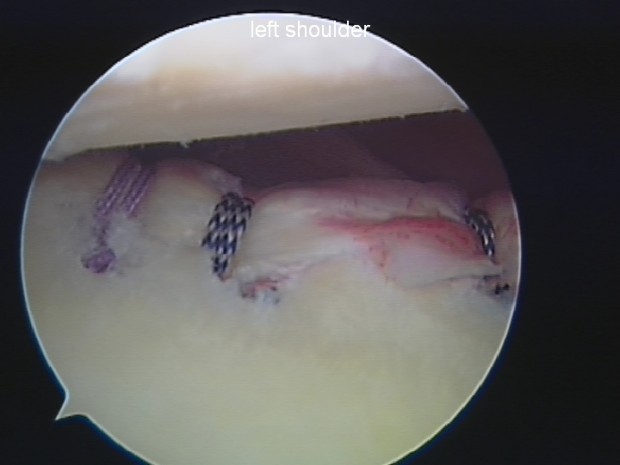

Dr Mike Walton working his magic, the arthroscope is in the posterior part of Dan’s shoulder while Mike is attaching an anchor near the biceps tendon.

Bankarts repair – you can see the 3 repairs clearly.